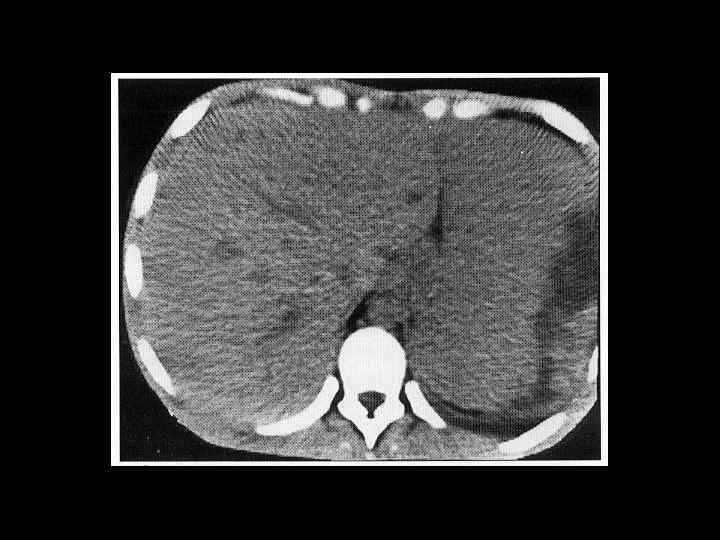

АКТУАЛЬНЫЕ ВОПРОСЫ РЕНТГЕНОЛОГИИ ЛУЧЕВАЯ ДИАГНОСТИКА ЗАБОЛЕВАНИЙ СЕЛЕЗЕНКИ Спленомегалия: Причины - Заболевания системы крови (гемолитические анемии, острые лейкозы, хронический миелоидный лейкоз, злокачественные лимфомы) - портальный цирроз печени - тромбоз селезеночной вены